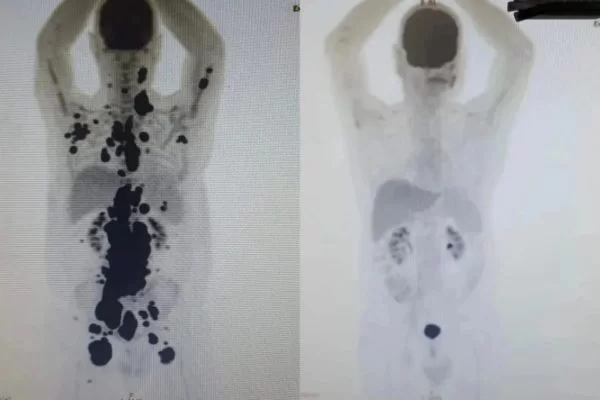

Paciente com câncer há 13 anos tem remissão completa de tumores em um mês